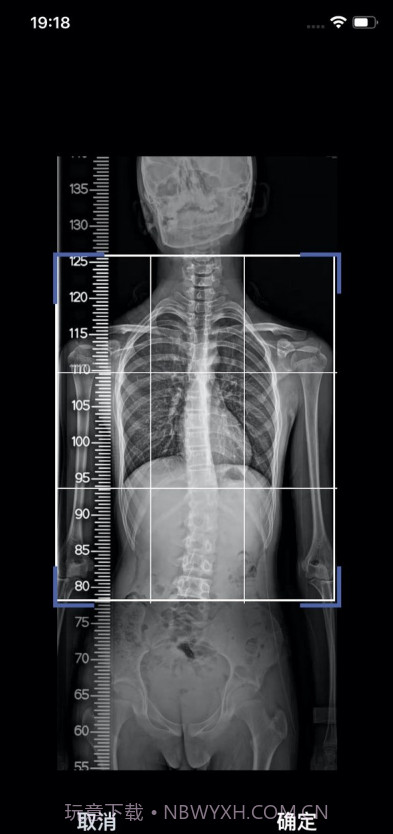

筠成矫形真的是一款很贴心的健康管理应用,特别适合坐办公室的白领和有姿势问题的青少年哦。它的个性化脊椎矫正方案通过摄像分析脊柱状况,真的能让你一目了然地看到自己的姿势问题。这款应用解决了不少人面对健康管理时的困扰:不再需要频繁去医院检查,你只需在家用手机拍照,就能获得专业的建议和提醒。最重要的是,它的定时休息提醒功能可以有效帮你避免久坐造成的健康隐患。总之,使用这款应用,你会发现自己更关注健康,生活质量也会随之提升!

摄像分析功能科技感十足,画面清晰

个性化脊椎矫正方案

使用摄像头拍摄分析,科技感满满